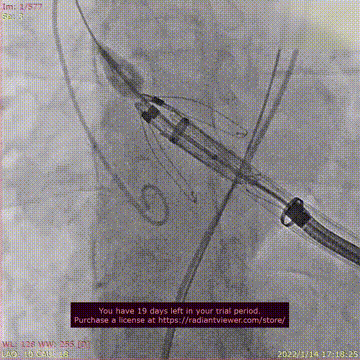

瓣膜释放过程

术后DSA影像图